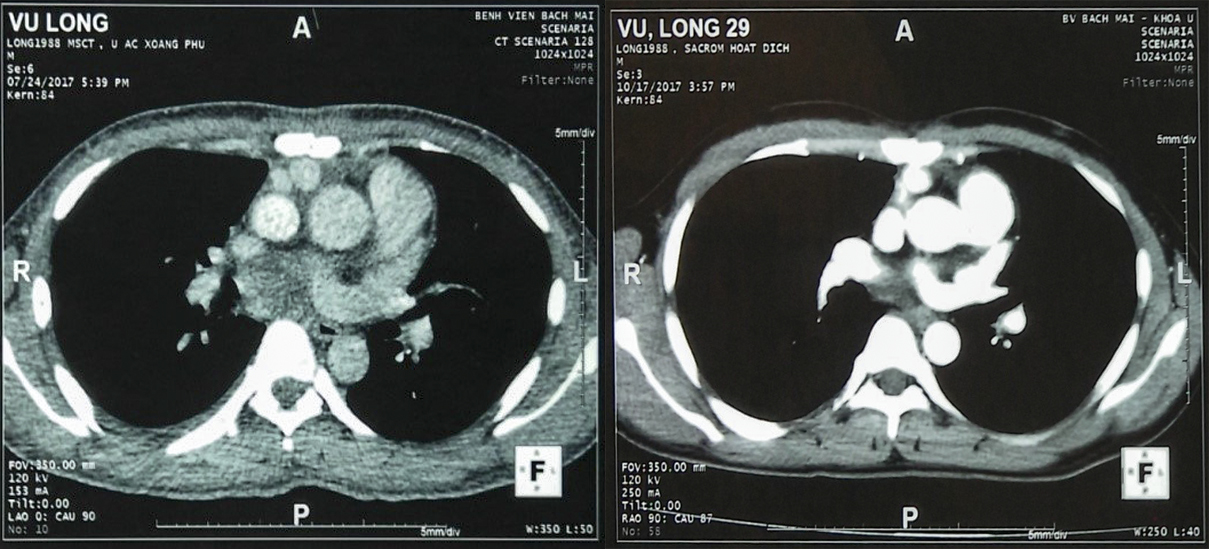

Hình 4: Hình ảnh chụp cắt lớp vi tính (CT) lồng ngực sau ba chu kỳ điều trị hoá chất: tổn thương đáp ứng hoàn toàn, khối u đã tiêu biến

Hiện tại bệnh nhân vừa kết thúc điều trị đợt 4 các chỉ số huyết học, chức năng gan thận hoàn toàn bình thường.

Bệnh cảnh của bệnh nhân trên đây là một trường hợp bệnh diễn biến nặng, phẫu thuật khó khăn, nhưng đáp ứng tốt với hóa chất, hy vọng bệnh nhân sẽ hoàn thành 6 chu kỳ hóa chất bổ trợ và đạt được đáp ứng lâu dài.